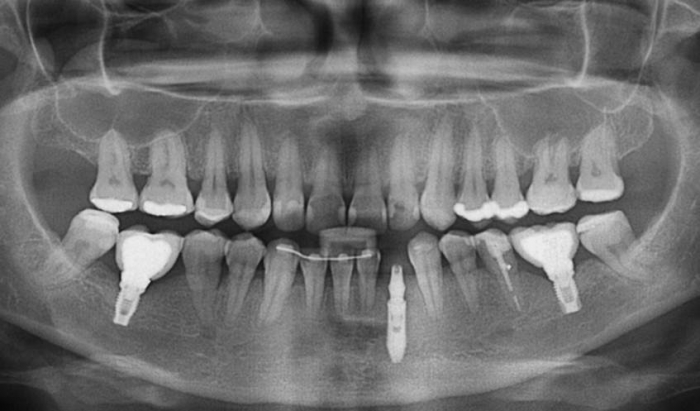

Raio X com próteses fixas em porcelana e encaminhada para extração de incisivo com reabsorção radicular